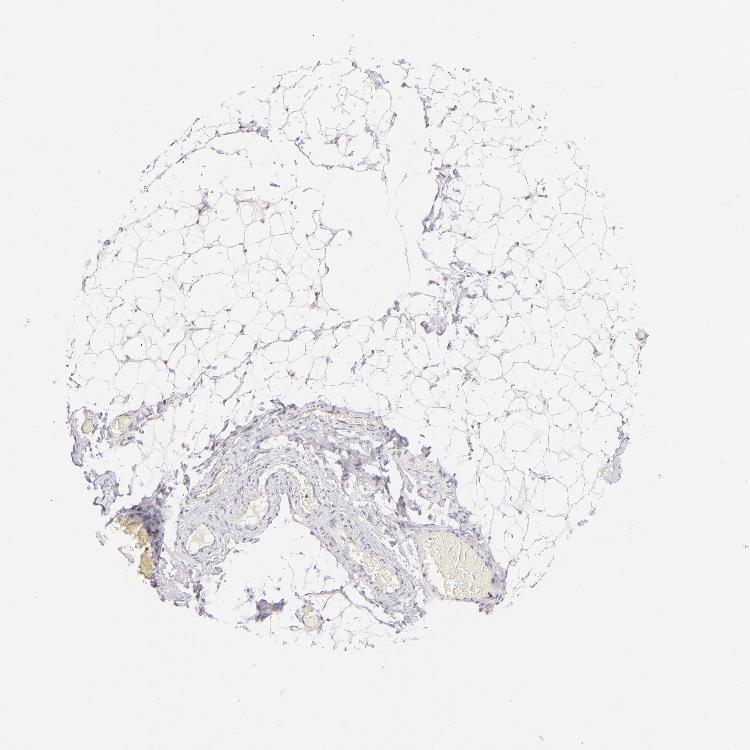

SOFT TISSUE 2 - Antibody stainingi

Antibody staining in the annotated cell types in the current human tissue is reported as not detected, low, medium, or high, based on conventional immunohistochemistry profiling in selected tissues. This score is based on the combination of the staining intensity and fraction of stained cells.

Each image is clickable and will lead to virtual microscopy that enables deeper exploration of all samples and also displays staining intensity scores, fraction scores and subcellular localization as well as patient and tissue information for each sample.

Antibody HPA003134Antibody CAB002625

Fibroblasts Not detectedNot detected

Peripheral nerve Not detectedNot detected